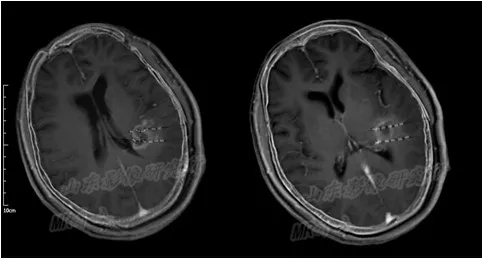

术中磁共振显示,4根穿刺针平行准确穿刺至病灶内

意识清醒的满女士,得知自己的肿瘤治疗这么快就结束了,有点不敢相信。

手术结束后,李成利主任给满女士做了CT扫描,进行剂量验证,一切都在计划标准范围之内,肿瘤顺利被消除,也没有任何并发症出现。